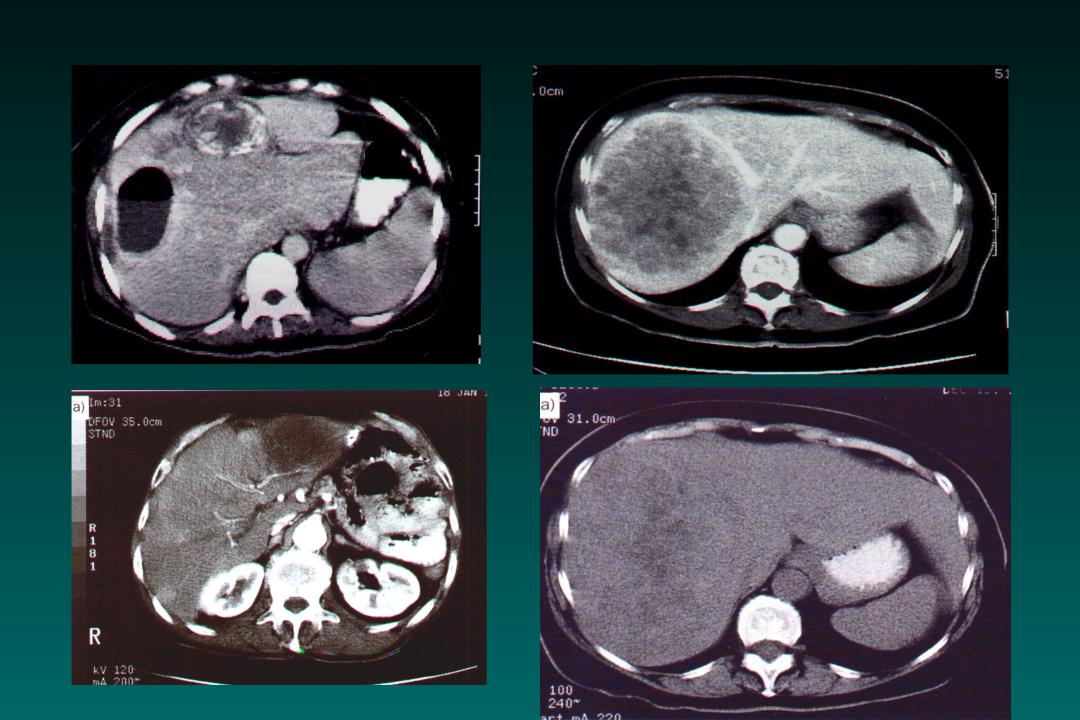

КТ ретроперитонеального фиброза: Изображения и диагностика